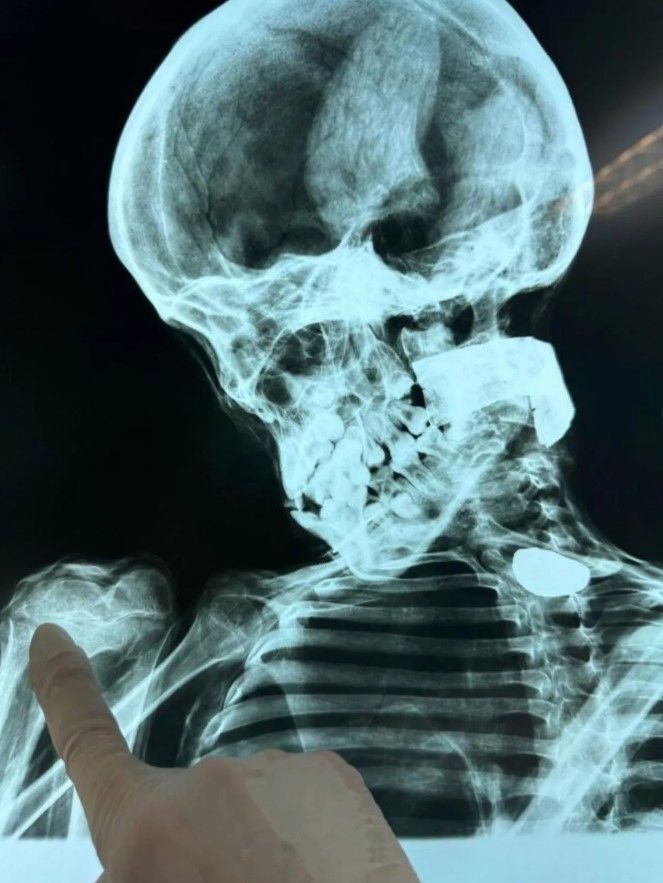

Журналіст Джойс Мантилья повідомив, що нещодавно виявлений "іншопланетний гуманоїд" матиме медичні скани, які будуть представлені під час слухань у Конгресі країни. У розмові з мексиканським журналістом і уфологом Хайме Мауссаном Мантилья сказав, що з нетерпінням чекає на можливість представити всі досягнення і останню інформацію про тіла. Він сказав, що істоти пройшли комп'ютерну томографію, і вони готові розкрити всі сюрпризи і новини в день слухань.

Говорячи про останній зразок, він сказав: "Це приголомшливий зразок, до якого я отримав доступ лише декілька днів тому. Ми помітили, що характеристики цього зразка дуже, дуже специфічні. На стопах ми побачили, що пропорція між пальцями і підошвою стопи набагато більша, ніж у будь-якого іншого. Ми представляємо докази комітету з питань культури, конференціям різних національностей, які аналізували тіла. Ми не збираємося залучати лялькарів та експертів з ремесел, ми збираємося залучати лише науковців, дані та прямі результати аналізу. Це, я вважаю, одне з найважливіших відкриттів не лише в історії Перу, але й у світовій історії. Походить із земель Перу, але це спадщина, яка належить людству, і ми всі маємо право знати відповідь і походження цих істот. Те, що ми будемо вимагати в Перу, і через Конгрес на цих слуханнях – це щоб було розпочато міжнародне розслідування. Немає жодного страху, вони не повинні боятися, тому що за ними стоїть наука".

Нагадаємо, раніше експерти зробили приголомшливу знахідку під час розтину тіл "мумій іншопланетян" із Перу. Вони побачили кістки та дивні металеві конструкції.